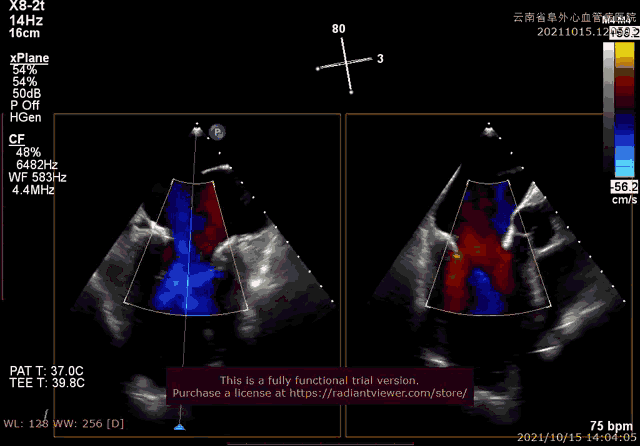

经过云南阜外医院结构性心脏病MDT团队综合讨论评估该患者病情后,患者为传统手术高危患者,瓣膜病变解剖无法行介入修复,决定进行MitraFix™经心尖二尖瓣植入。术前心脏CTA二尖瓣D形瓣环面积折算直径34mm, 模拟植入34号介入二尖瓣膜(外经约40mm)后左心室NeoLOVT面积可(>150mm2)。手术在单纯超声引导下完成,采用左侧肋间4cm微创切口心尖入路,在超声引导下,输送系统准确跨瓣,并将瓣膜准确释放于二尖瓣瓣瓣环,瓣膜释放后支架贴合牢固,无瓣周漏及瓣内反流,二尖瓣前向血流通畅,平均压力阶差2mmHg,左心室流出道通畅,流出到血流速度为2.3m/s,平均压力阶差8mmHg(图2-3,视频1)。顺利撤出输送系统,关闭心尖切口,手术顺利结束。

图2:术中TEE见左心增大,收缩期瓣叶广泛脱垂,心功能降低